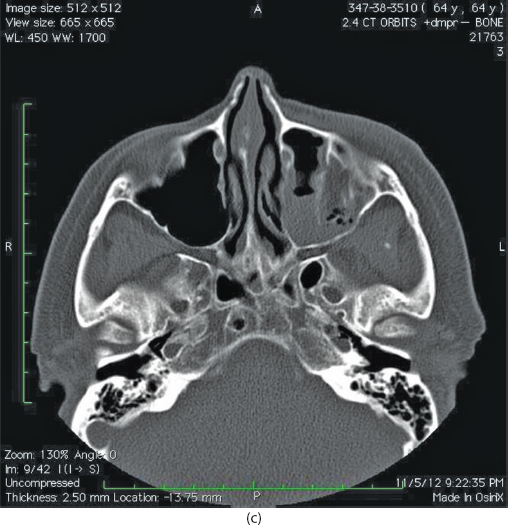

Isolated orbital floor fractures (blowouts) are often the result of impact injury to the globe resulting in a sudden increase in intraorbital hydraulic pressure. This kinetic energy is transmitted in an inferior and medial vector to the orbital floor (hydraulic theory) (Figure 13.1). Alternatively, the posterior transmission of a direct blow to the infraorbital rim causes buckling and resultant fracture of the orbital floor (buckling theory) (Figure 13.2). Fractures of the orbital floor can increase the volume of the orbit with resultant enophthalmos and hypoglobus. These can be highlighted on preoperative (Figure 13.3a–c) and postoperative (Figure 13.4a–c) computed tomographic (CT) scan imaging. In addition, the inferior rectus or periorbital soft tissue can become entrapped within the fracture line, resulting in restriction of extraocular eye movements. Table 13.1 indicates the special equipment used to surgically manage this injury.